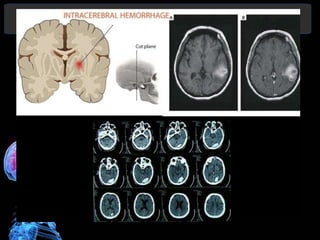

• TC permite mostrar la presencia de una

• Evidencia el tamaño, localización, edema

satelite, desplazamientos por efecto de

masa, invasión ventricular y la

hidrocefalia.

• Permite orientar el tratamiento y estimar

un pronóstico

LOCALIZACIÓN

• 50% en áreas de los núcleos grises basales:

– Putaminales, por compromiso de las arterias lentículo-estriadas

– Talámicas por afectación de las arterias tálamo-geniculadas),

• Lobares (31%) , estando la mitad próximos a la

encrucijada ventricular

– Lóbulo temporal- aneurismas de cerebral media

– Lóbulo frontal-aneurismas de comunicante anterior

• Cerebelosas (10%) con lesiones en las arterias

cerebelosas postero-inferiores o cerebelosas superiores

• Tronco cerebral (10%), sobre todo a nivel

protuberancial con compromiso de ramos perforantes

de la arteria basilar.